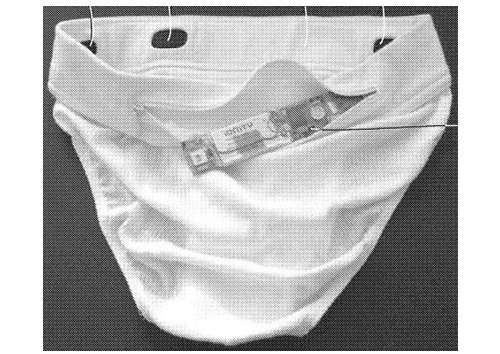

Anziché ricorrere ai tradizionali strumenti di misurazione, i sensori integrati negli slip sono pensati per misurare la velocità dell’impulso circolatorio, un dato che viene ritenuto potenzialmente indicativo della pressione. Una rilevazione che può essere effettuata per tutto il tempo nel quale gli slip vengono indossati, assicurando così un monitoraggio non invasivo e continuativo. A questo scopo, i sensori sono inseriti nel tessuto all’altezza della vita.

Nel brevetto, disponibile a questo indirizzo si parla di “un sistema per monitorare/misurare i segni vitali di un paziente, in particolare la pressione del sangue, che comprende una pluralità di elettrodi inseriti nel girovita di un indumento intimo”.